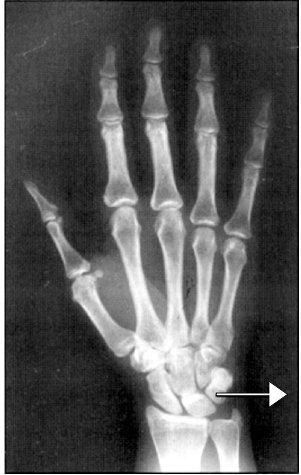

Ao se realizar um raio X da mão em Postero Anterior, marque a alternativa em que a estrutura está em destaque:.

A

Osso Manúbrio.

B

Osso Piramidal.

C

Osso Navicular.

D

Osso Cubóide.

E

Osso Cuneiforme.